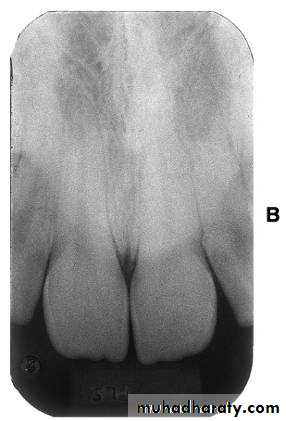

Premolar bitewing. A, Film placement. B, Resultant radiograph.

AB